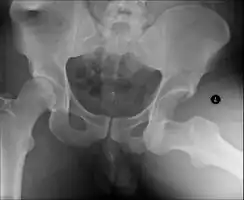

| X-ray showing a joint dislocation of the left hip. | |

Anterior-posterior (AP) X-rays of the pelvis, AP and lateral views of the femur (knee included) are ordered for diagnosis.[13] The size of the head of the femur is then compared across both sides of the pelvis. The affected femoral head will appear larger if the dislocation is anterior, and smaller if posterior.[14] A CT scan may also be ordered to clarify the fracture pattern.